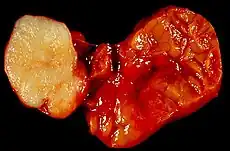

Benign tumour of the submandibular gland, also known as pleomorphic adenoma, presented as a painless neck mass in a 40-year-old man. At the left of the image is the white tumor with its characteristic cartilaginous cut surface. To the right is the normally lobated submandibular salivary gland.